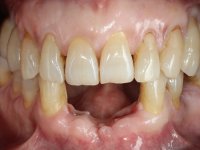

The patient came to the consultation saying that a “hole” had appeared in the gum area next to an implant. He did not report having had pain or any type of swelling.

Female patient, 62 years old, smoker. 10 years ago, an implant had been placed in the area of teeth 41 and 42 to rehabilitate the lack of these two teeth with a two-element bridge. After the imaging exam, bone loss was observed next to the implant compatible with peri-implantitis. The buccal bone wall next to the implant showed extensive resorption, with the buccal surface of the implant in contact with the soft tissues and in a certain area a hole allowed the implant to be visualized through the gingival tissue. Teeth 42 and 32 already showed some mobility.